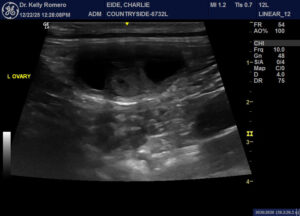

8 month old FI Golden with no clinical symptoms. pcDVM did wellness blood work one week ago- WBC was 35,000 with all cell lines elevated. Two weeks ago, owners notes some vaginal bleeding (mild). One week ago (when blood work run), vaginal discharge became more clear (still mild) and behaviorally, the male neutered dog in the house became interested and the female is receptive. Only findings I am wondering about were both ovaries appear to have active follicles (was expecting that in just one) and quite plump mes. lns. VIN search=not normal to have elevated WBC during estrus. Thoughts?

Looks like cystic ovaries and early pyometra to me and juvenile or reactive LN. OVH if not intended for breeding.